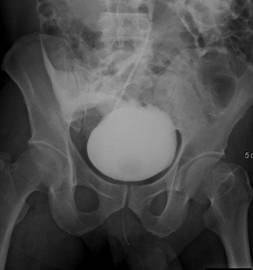

【112-1 醫學(五) 第74題】一名成年男性病人車禍後主訴下腹部疼痛和血尿,逆行性膀胱攝影檢查呈現如附圖。下列有關膀胱的初診斷何者最恰當?

這題的關鍵在於辨識逆行性膀胱攝影(retrograde cystography)中,顯影劑從膀胱外滲到腹腔,包圍住腸道(bowel loops)的影像特徵。車禍外傷史加上血尿,強烈暗示泌尿系統受損。